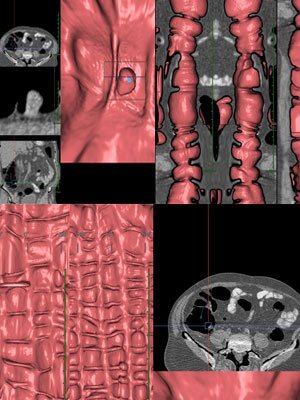

コロノグラフィー(CTC)検査

• 64列の高性能CT装置で委託検査を多数行っています

• 要予約にて、検査パス表・低残渣食・下剤をお渡しします

• 一度、来院して頂く必要があります。時間の確認をお願いします

CTC